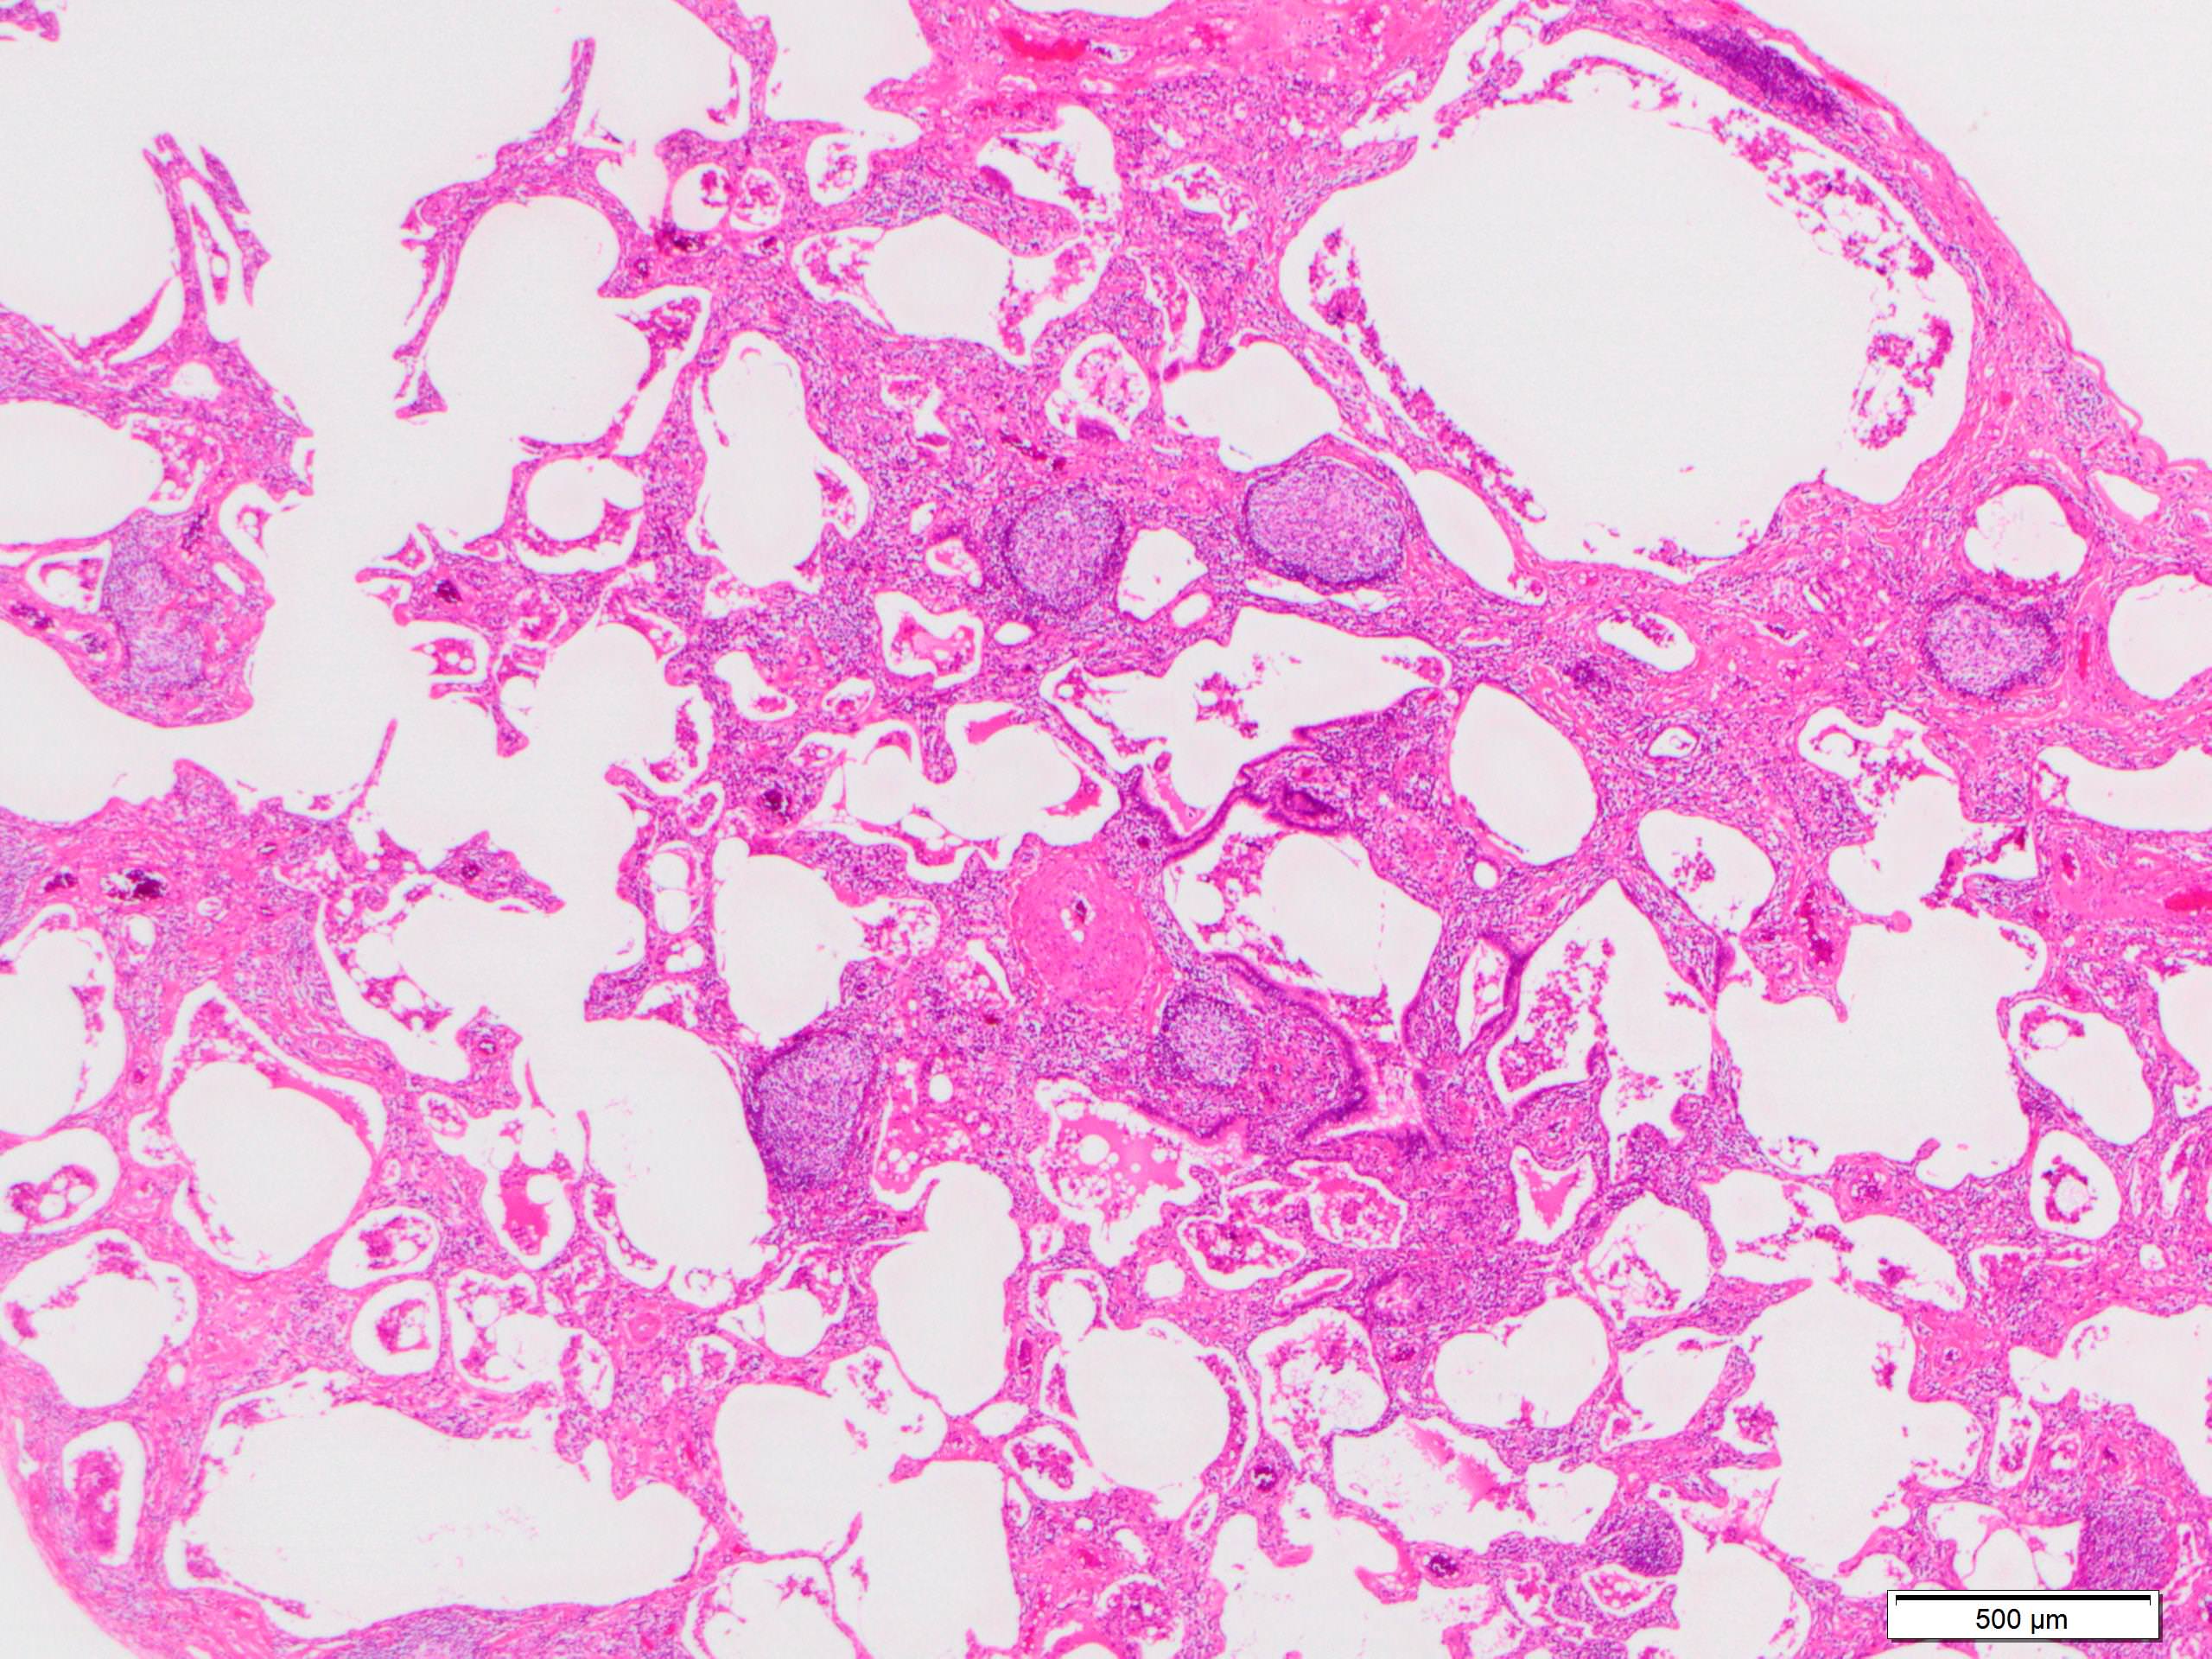

Microscopic (histologic) description

- Since there are few specific findings for NSIP pattern, it is essential to exclude other lung diseases on histology (Am J Respir Crit Care Med 2008;177:1338)

- Characteristic findings of NSIP pattern

- Diffuse and uniform inflammation ("temporal homogeneity") on low power of alveolar wall, bronchovascular bundles and pleura

- There are usually no normal alveolar walls in the affected lobules

- Cellular or fibrotic change

- Lymphocytic or plasmacytic infiltration

- Loose fibrosis

- Lung architecture is frequently preserved

- "Cellular NSIP" or "fibrotic NSIP" can be stated specifically in pathologist report

- Diffuse and uniform inflammation ("temporal homogeneity") on low power of alveolar wall, bronchovascular bundles and pleura

Microscopic (histologic) images

Scroll to see all images.

Contributed by Akira Yoshikawa, M.D.

Images hosted on other servers:

Contributed by Akira Yoshikawa, M.D.

Images hosted on other servers: